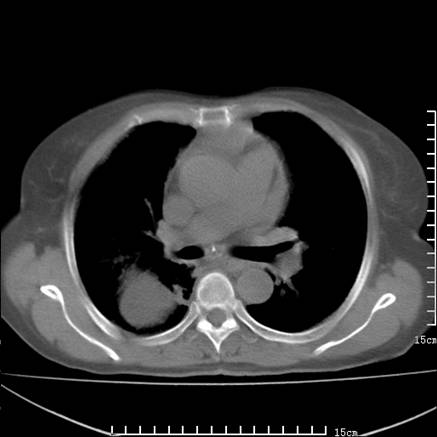

女,王某,58岁,咳嗽三个月余,基层医院二个月前诊为肺结核,用抗结核药二个月无明显疗效。

心包积液致肺瘀血.右侧周围型肺癌伴肺内转移,中间裂积液,叶间胸膜肥厚.右上肺大泡,右侧胸膜肥厚.

双肺继发型tb,心功能不全并肺淤血、心包、双侧叶间裂积液,肺大泡,右下胸膜肥厚钙化。